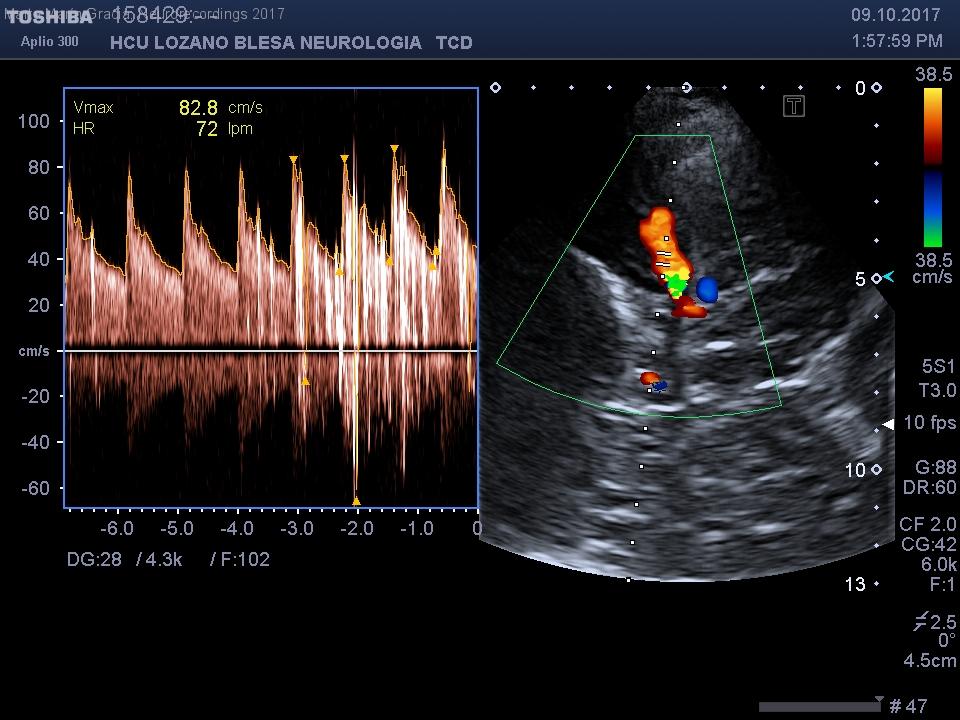

Hombre | 41 años

Diagnóstico final: IIctus criptogénico y foramen oval permeable

Neurología: Patología cerebrovascular

Resumen del caso

Varón 43 años, fumador, independiente para ABVD y Rankin 0. Con antecedentes de dislipemia, TCE a los 9 años con Epilepsia 2ª, deterioro cognitivo leve. Intervenido de craniectomía anterior y posterior con craneoplastia. En tratamiento con carbamazepina 400...